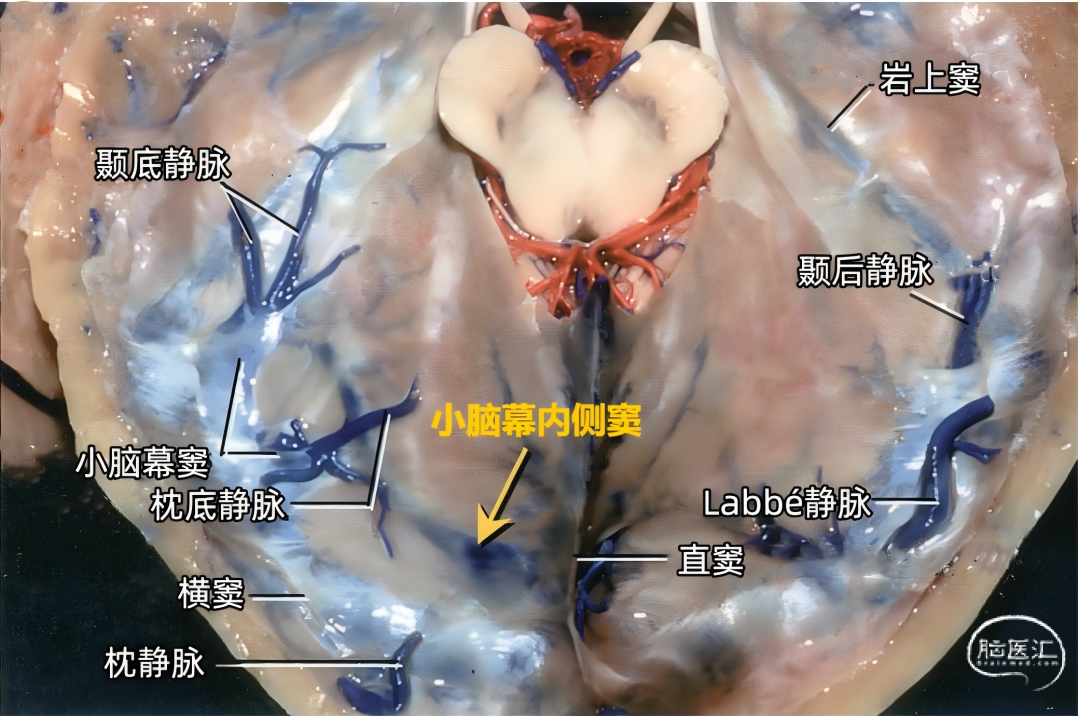

颞叶外侧面的皮层静脉可引流入横窦(上图),但在流入横窦之前,它们常向内沿颞叶底面进入小脑幕的短窦,此窦进入横窦末端之前在小脑幕内走行大约1cm。来自颞叶和枕叶底面的皮层静脉通常汇入外侧小脑幕窦。 Labbé静脉通常终于横窦(上图),但也可弧形围绕大脑半球下缘汇入外侧小脑幕窦。▼9.小脑幕窦

每侧小脑幕有两个恒定但不对称的静脉窦,即内侧小脑幕窦和外侧小脑幕窦。 内侧小脑幕窦由小脑上表面的回流静脉汇聚而成。内侧小脑幕窦向内侧引流入直窦,或直窦与横窦的汇合处。 外侧小脑幕窦由颞叶和枕叶基底面和外侧面的回流静脉汇聚而成。外侧小脑幕窦起自小脑幕的外侧部分,并向外侧引流入横窦的末端。 下图示抬起小脑幕,可见来自小脑、在小脑幕下缘入窦的桥静脉。左侧黄色箭头显示一支较大的静脉自小脑上表面进入内侧小脑幕窦。右侧红色箭头显示一支粗大的来自小脑上表面的桥静脉在窦汇前方进入内侧小脑幕窦。

下图示汇入外侧小脑幕窦的颞底静脉、枕底静脉。左侧红色箭头指示左侧汇入小脑幕窦属支的颞底长静脉。颞底静脉汇入有多个属支的小脑幕窦。右侧黄色箭头显示汇入右侧小脑幕窦的静脉属支。 下图示(左侧)颞底静脉和枕底静脉汇聚于两个横窦内侧的短小脑幕窦。(右侧)Labbé静脉和颞后静脉直接引流入横窦。左侧小脑幕的另一个窦(小脑幕内侧窦)(黄色箭头)接受来自小脑的引流,向内侧经过小脑幕汇入窦汇。

下图示右侧枕底静脉,颞底静脉。从后颞下入路抬起颞底到达小脑幕游离缘时,除了可能牺牲Labbé静脉和来自颞叶、枕叶外侧面的静脉外,还可能需要牺牲多条汇入小脑幕窦的颞底静脉和枕底静脉。

▼2.Labbé静脉

Labbé静脉也称下吻合静脉,是跨越颞叶外侧,连接外侧裂与横窦之间的最大吻合静脉。它通常起自外侧裂中部,行向后下,进入横窦前部。 Labbé静脉经过颞叶表面的位置有可能非常靠后甚至位于颞叶的最后界,或非常靠前达颞叶前1/3的外侧面。在此研究的20例半球中,12例Labbé静脉位于颞中静脉水平,6例位于颞后静脉水平,2例位于颞前静脉水平。有时会有两条Labbé静脉,其中后支通常会粗大一些。

下图示横窦和小脑幕窦的分支。抬起颞叶的后部,暴露进入横窦的Labbé静脉、颞后静脉和枕后静脉,从颞叶底面进入小脑幕窦的颞底静脉。

下图示小脑幕的上面观。右侧Labbé静脉和颞后静脉直接引流入横窦。

小脑幕组(上图 绿色)的桥静脉汇入行经小脑幕的静脉窦,即小脑幕窦或小脑幕附近的横窦和岩上窦。本组静脉引流颞叶外侧面和底面、枕叶的底面,包括颞底静脉、枕底静脉和来自颞叶外侧面的降静脉,如Labbé静脉。 除Labbé静脉外,这些静脉虽然有可能进入横窦,但大多数围绕半球的下缘汇聚于枕前切迹到达外侧小脑幕窦。而Labbé静脉通常汇入横窦。大脑底面的桥静脉汇入静脉窦之前,经常粘连于与中颅窝底硬膜和小脑幕表面。 从外侧面引流入小脑幕窦的静脉包括颞前静脉、颞中静脉、颞后静脉和Labbé静脉。

从下表面引流入小脑幕窦的静脉包括颞底前静脉,颞底中静脉、颞底后静脉和枕底静脉。 内侧小脑幕窦接受来自小脑的静脉血流,并加入直窦。基底窦位于斜坡。 大脑镰组(上图 紫色)由直接或经由大脑内静脉、基底静脉和大脑大静脉汇入下矢状窦或直窦的静脉构成。汇入直窦的静脉(上图 紫色)或其属支,引流胼胝体附近部分的额叶、顶叶和颞叶内侧部,此组静脉的引流区域大致相当于大脑边缘叶,包括终板旁静脉,额眶后静脉、嗅静脉、胼周前静脉、胼周后静脉,钩回静脉、海马前静脉、颞内侧静脉和距状前静脉。

在颞底的后方可能遇到许多桥静脉(下图),这些静脉包括颞、枕、颞底、枕底静脉和Labbé静脉,伤及这些从大脑半球下表面进入横窦和小脑幕窦的静脉,经常会产生某种程度的静脉梗塞和颞叶水肿。这些静脉闭塞以后,有可能导致对侧肢体偏瘫,其中面部和上肢较下肢更明显,优势半球受累还可能导致失语。 在横窦和岩上窦结合部抬起颞叶时经常遇见的难题是有许多来源于颞叶外侧面和底面的静脉聚集在这一区域(上图)。颞下入路手术后遗症的产生往往是因为Labbé静脉的闭塞;但是术中单纯烧闭Labbé静脉的情况并不多,因为当颞下入路需要在颞叶内侧暴露小脑幕缘时,也需要牺牲其他许多这一区域的桥静脉。